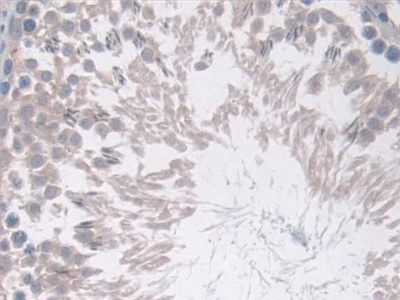

- ApplicationsWB; IHC

The antibody is a rabbit polyclonal antibody raised against COX-1. It has been selected for its ability to recognize COX-1 in immunohistochemical staining and western blotting.

Immunohistochemistry: 5-20µg/mL;